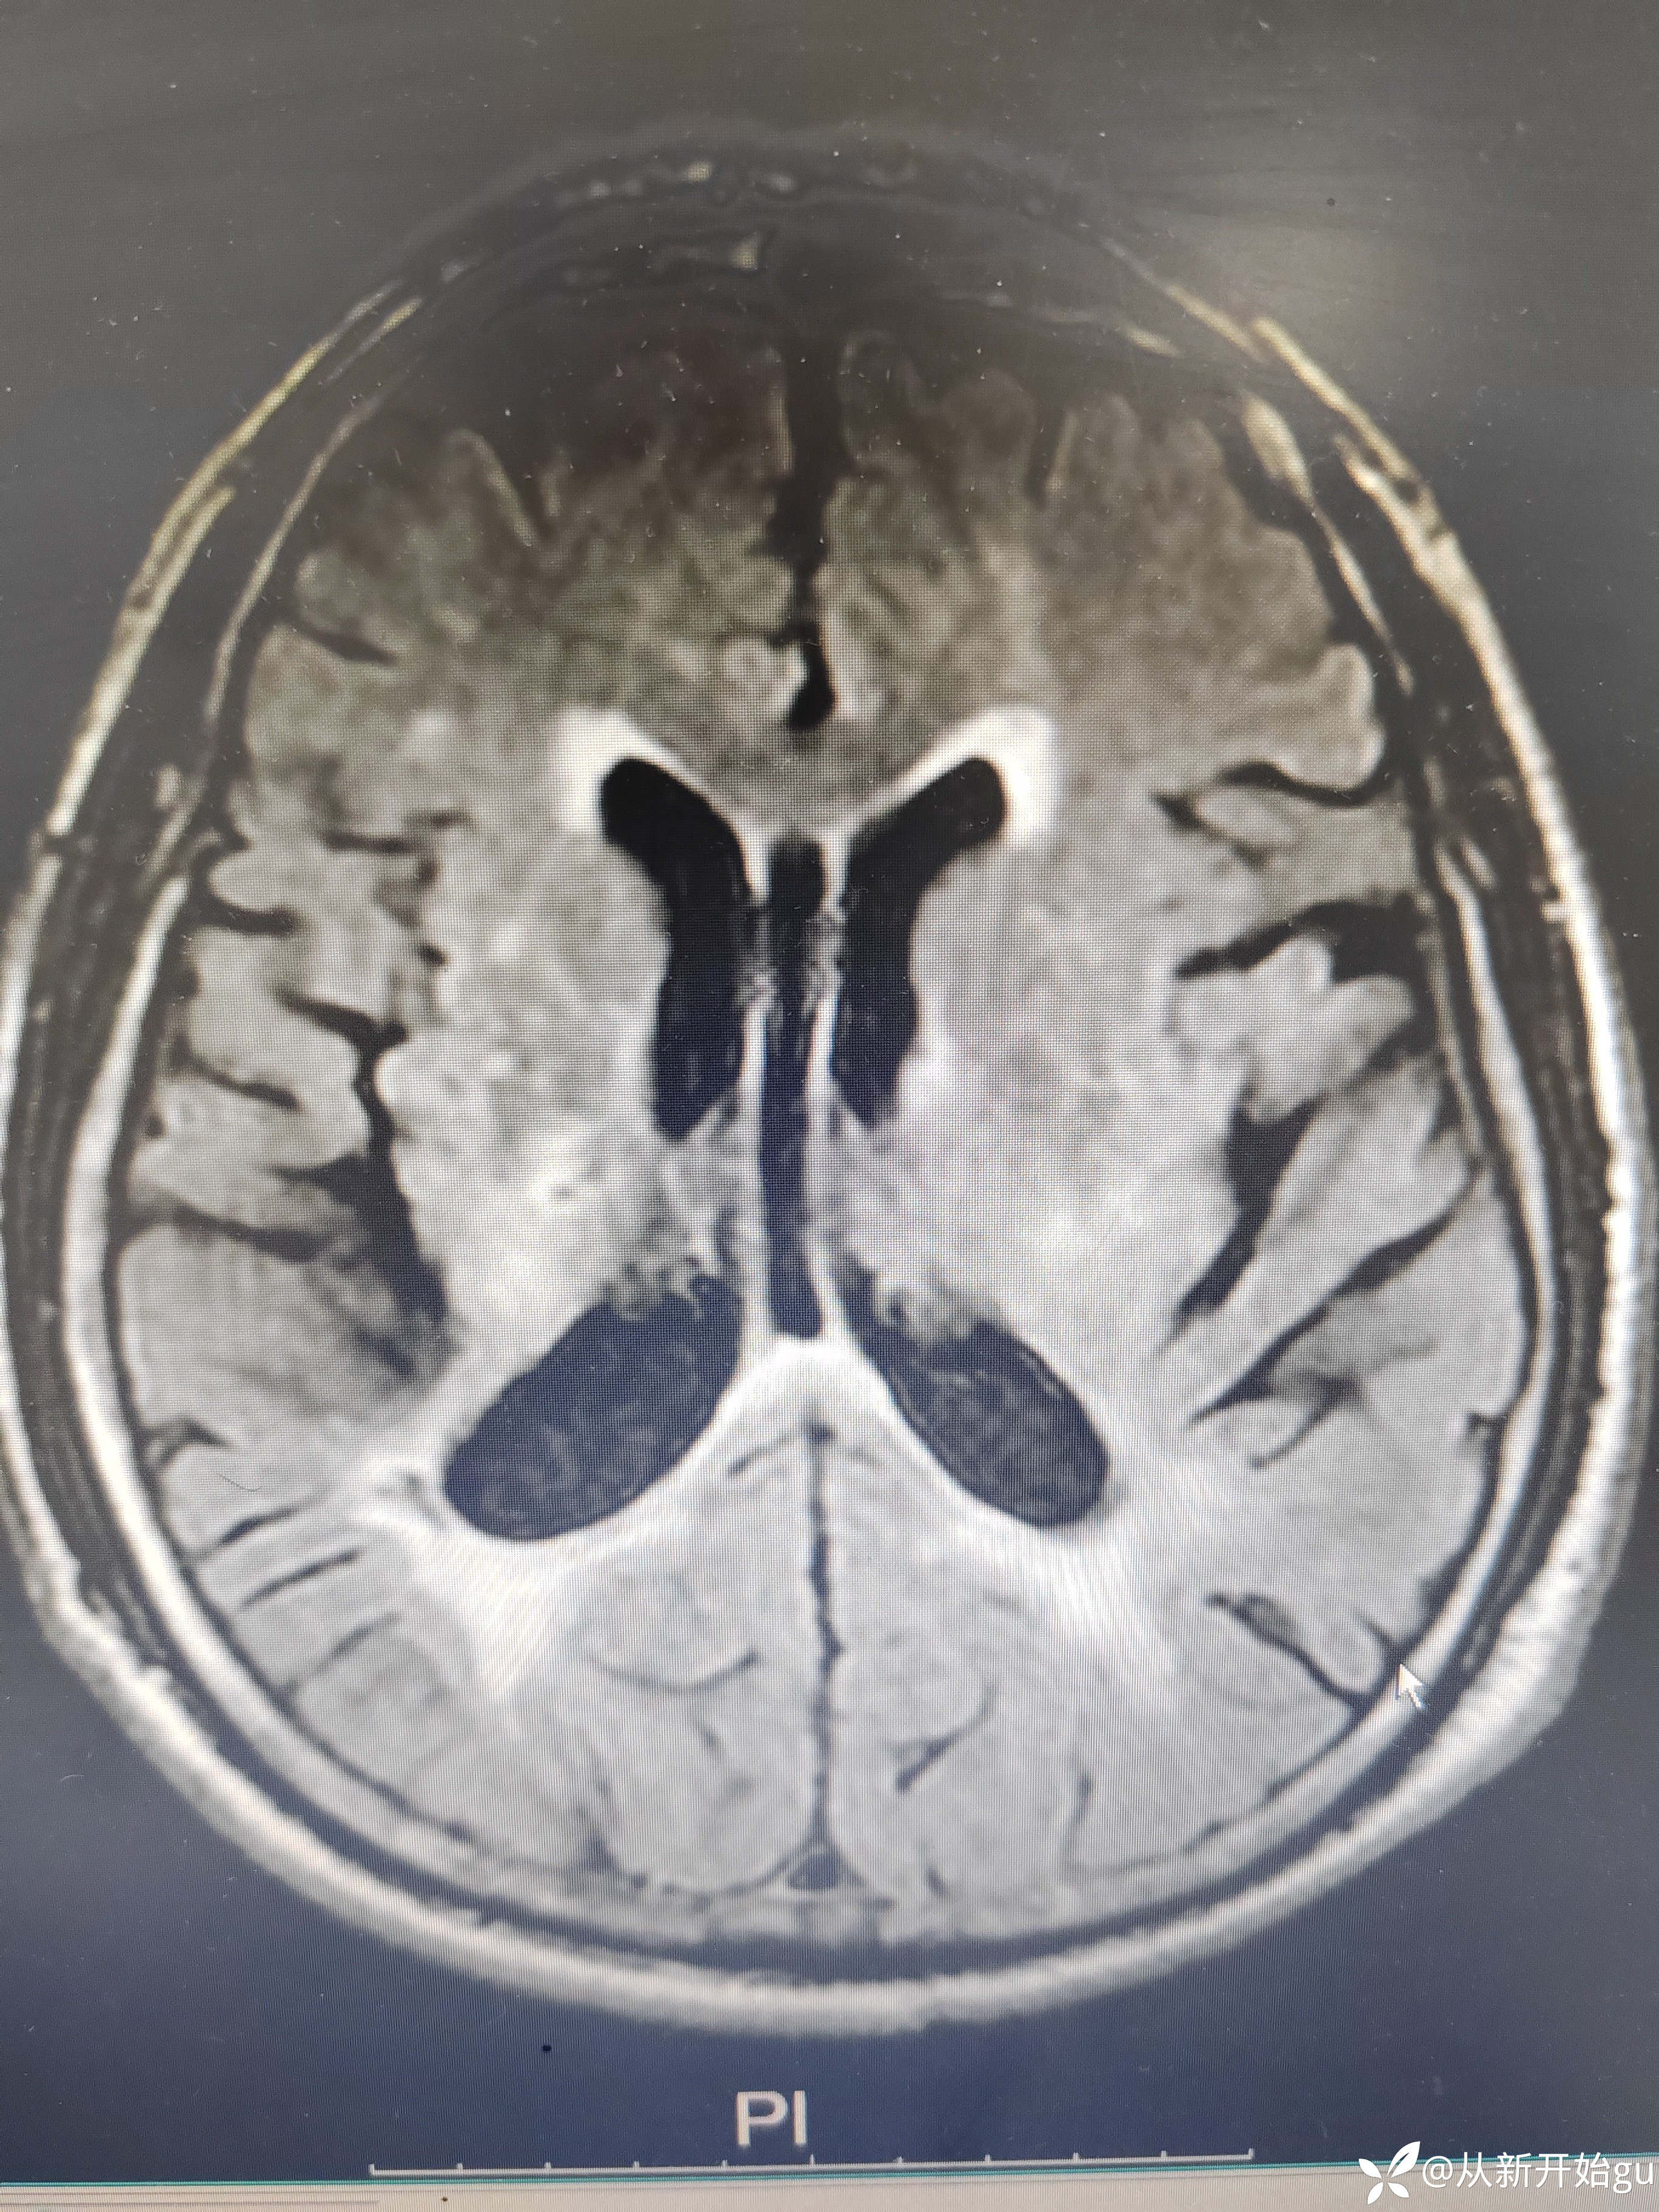

患者男性53岁,主因被发现左下肢活动障碍2.5小时来院,(患者下夜班,于上午9点休息,下午3点醒后出现症状)。既往脑梗死病史9个月,遗留言语不利及口角歪斜的症状。查体:右侧鼻唇沟稍浅,神舌右偏,左侧下肢肌力4级,左侧指鼻试验欠稳准,左侧巴氏征阳性。外院完善颅脑CT无出血改变。来院后完善核磁检查如图所示。